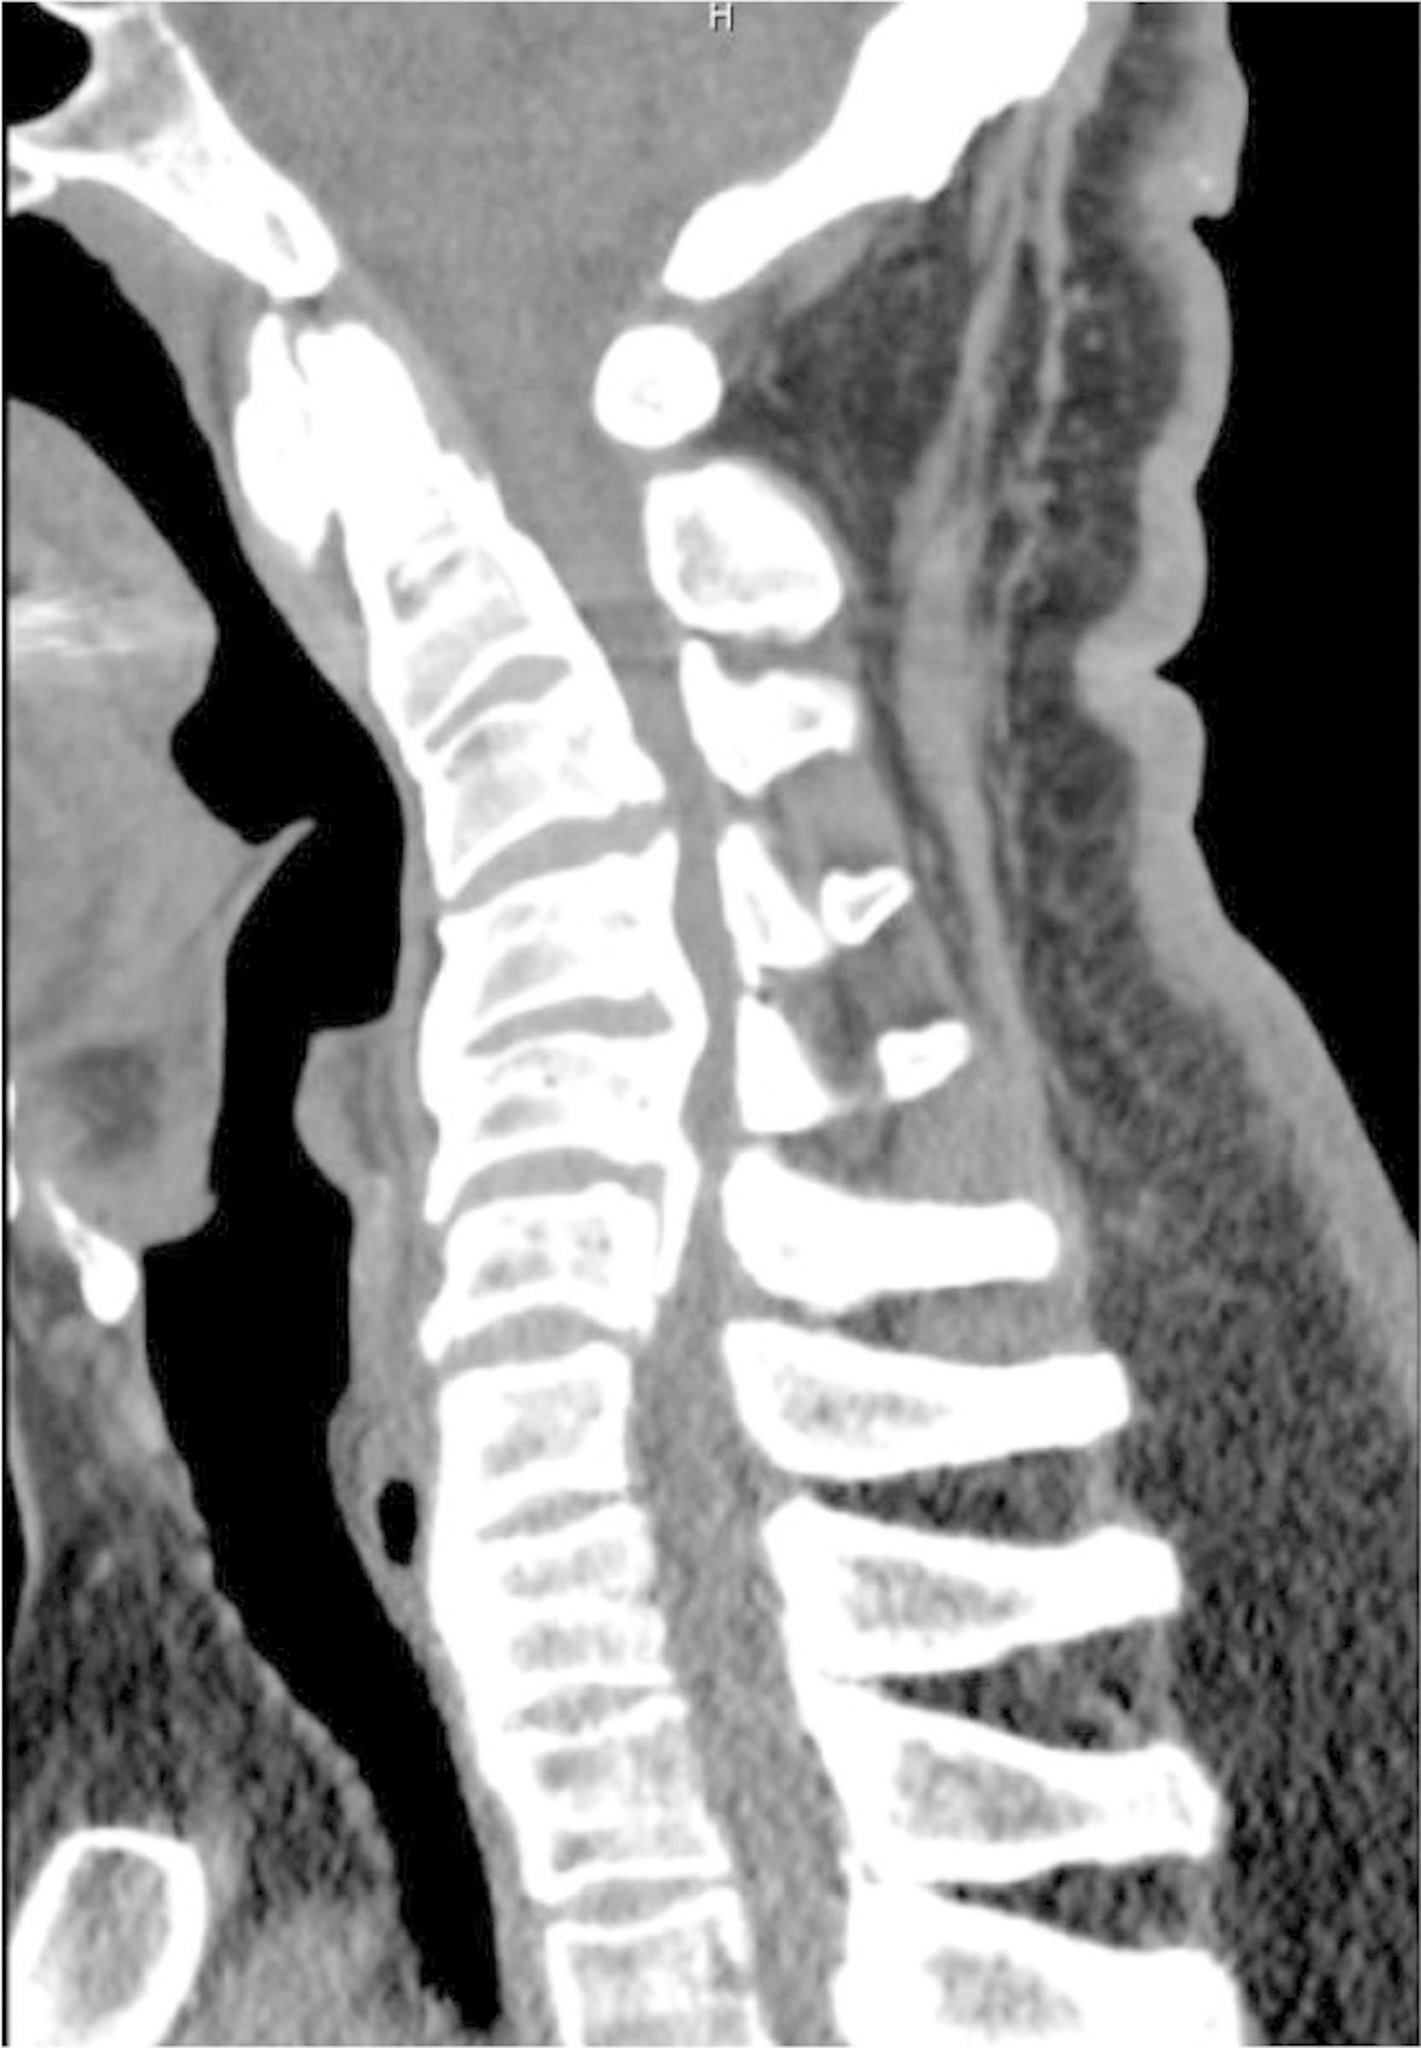

Síndrome del cordón blanco y tetraplejía aguda después de la descompresión cervical posterior: reporte de un caso

Un hombre de 55 años se somete a descompresión cervical posterior e instrumentación por mielopatía cervical progresiva y desarrolla síndrome del cordón blanco (WCS) en el posoperatorio con tetraplejía aguda.

La WCS es una complicación poco común de la cirugía de columna que se cree que se debe a una lesión por reperfusión. Diagnosticamos WCS en nuestro paciente mediante un examen posoperatorio que consistió en tetraplejía aguda y resonancia magnética que reveló un aumento de la señal en el cordón. En este caso, utilizamos dexametasona intravenosa y una presión arterial media superior a 90 mm Hg, lo que dio como resultado un examen clínico notablemente mejorado.